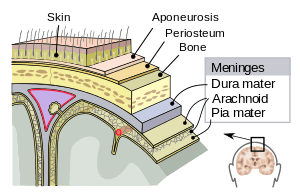

The periosteum appears just below the skin. | |